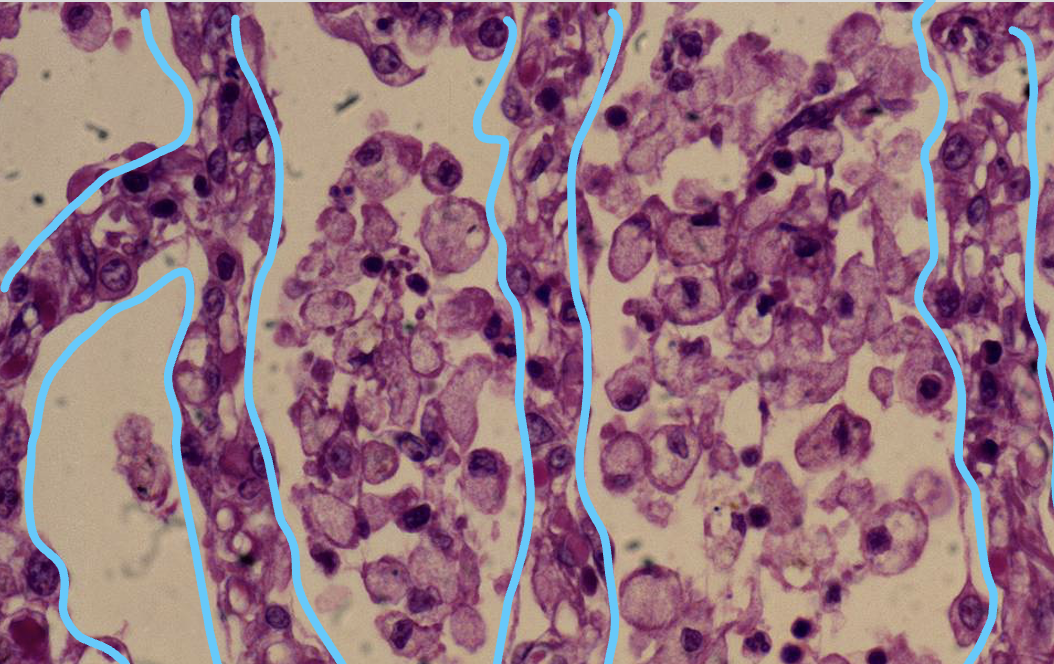

Neutrophils in pulmonary alveolar airspaces, acute bronchopneumonia